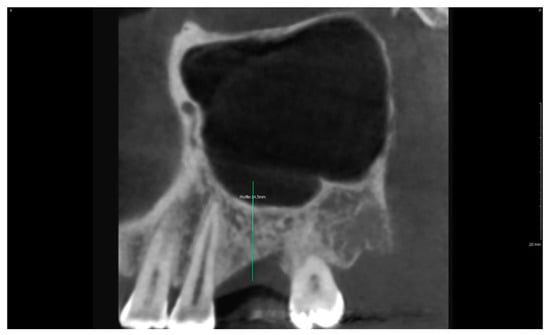

2.6. Case Study